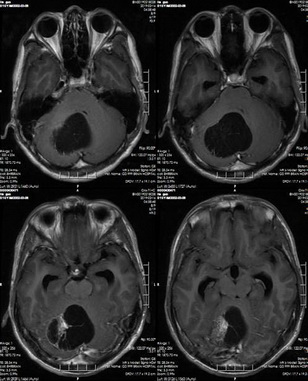

入院后,神经外科医生为小林完善相关检查,头部MRI提示:1.右侧小脑半球占位性病变,考虑偏低级别肿瘤性病变,毛细胞型星形细胞瘤可能;2.幕上梗阻性脑积水并脑室旁间质水肿;3.小脑扁桃体下疝。

术前MR示:1.右侧小脑半球占位性病变,考虑偏低级别肿瘤性病变;2.幕上梗阻性脑积水并脑室旁间质水肿;3.小脑扁桃体下疝。